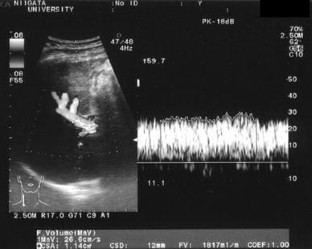

Patent ductus venosus (PDV) is a rare condition of a congenital portosystemic shunt from the umbilical vein to the inferior vena cava. This report presents the case of an adult patient with PDV, who was successfully treated with laparoscopic shunt division. A 69-year-old male was referred with hepatic encephalopathy. Contrast-enhanced CT revealed a large connection between the left portal vein and the inferior vena cava, which was diagnosed as PDV. The safety of a shunt disconnection was confirmed using a temporary balloon occlusion test for the shunt, and the shunt division was performed laparoscopically. The shunt was carefully separated from the liver parenchyma with relative ease, and then divided using a vascular stapler. Portal flow was markedly increased after the operation, and the liver function of the patient improved over the 3-month period after surgery. Although careful interventional evaluation for portal flow is absolutely imperative prior to surgery, a minimally invasive laparoscopic approach can be safely used for treating PDV.

Fig. 1